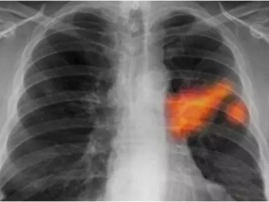

油烟污染与肺结节形成的潜在关联探究

热搜新闻 125

你知道吗?最近有个话题在朋友圈里炒得火热,那就是肺结节的形成可能与油烟有关。是不是觉得有点不可思议?别急,让我带你一探究竟,揭开这个神秘的面纱。油烟,那个看不见的“隐形杀手”想象厨房里弥漫着各种美食的香气,而你正忙碌地烹饪着。这时,你是否注意到,锅里升腾的油烟在空气中飘荡?这些看似无害的油烟,其实可能隐藏着巨...